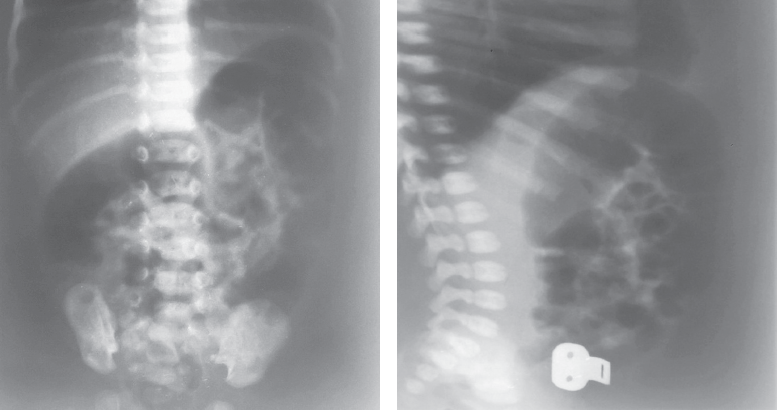

В хирургический стационар поступил ребенок на 2-е сутки жизни с клиникой кишечной непроходимости. По данным обзорной рентгенографии и ирригографии заподозрена болезнь Гиршпрунга (рис. 5, 6).

Рис. 5. Обзорная рентгенограмма брюшной полости

Fig. 5. Plain abdominal X-ray

Ирригография является обязательным исследованием у всех детей с подозрением на болезнь Гиршпрунга [2]. Чувствительность и специфичность метода по литературным данным достигает 70 и 80 % соответственно. Хорошо известно, что диагностическая значимость ирригографии в определении переходной зоны у новорожденных с болезнью Гиршпрунга меньше, чем у детей более старшего возраста (65 против 75 %) [3]. I.R. Diamond et al [4]. описали возможные предрасполагающие факторы получения ложноположительных результатов при выполнении контрастного исследования у пациентов с болезнью Гиршпрунга, одним из них является возраст ребенка. У детей в возрасте 30 сут жизни было больше ложноположительных результатов, чем у пациентов младшего возраста. Срок выполнения рентгенологического обследования зависит от нескольких факторов, главным из которых является эффективность опорожнения толстой кишки. Обследование целесообразно выполнять не сразу после поступления новорожденного в стационар, а отсроченно, после купирования явлений Гиршпрунг-ассоциированного энтероколита, чтобы исключить сужение кишки, связанное с ее спазмом на фоне воспалительных явлений. Конечно, это не касается ситуаций, когда есть клиника некупирующейся кишечной непроходимости, либо признаки «токсического» мегаколона. В этих случаях ирригография обязательно проводится непосредственно при поступлении ребенка в стационар. В остальных случаях, когда декомпрессия кишечника эффективна, исследование может быть отложено на несколько дней, до полной стабилизации состояния и нормализации клинико-лабораторных показателей. Контрастирование толстой кишки у детей с клиникой низкой кишечной непроходимости носит не только диагностический, но и лечебный характер, особенно при синдромах мекониальной пробки и суженной левой половины толстой кишки, которые могут быть причиной для постановки ложноположительного диагноза болезни Гиршпрунга. Надо отметить, что ирригография, выполненная в первые дни жизни ребенка сразу после появления клиники непроходимости, и отсроченное исследование могут отличаться друг от друга. На представленных рентгенограммах одного и того же ребенка с разницей в две недели видны существенные различия (рис. 8, а, b). Если на первичной ирригограмме можно оценить лишь правильность расположения толстой кишки и наличие в ней большого количества содержимого, то при исследовании через 2 недели видны четкие признаки ректосигмоидной формы болезни Гиршпрунга с наличием зоны сужения и воронкообразным супрастенотическим расширением.

Рис. 8. Ирригография; а — вторые сутки жизни; b — две недели жизни

Fig. 8. Contrast enema. а – second day of life; b – two weeks of life

Еще одним доводом за выполнение отсроченных ирригограмм у новорожденных с подозрением на болезнь Гиршпрунга может служить тот факт, что при раннем исследовании можно увидеть выраженное сужение толстой кишки, которое у новорожденного может быть признаком не только аганглиоза, но и иметь другие причины.

Считается, что чем более выражена разница в диаметре кишки при ирригоскопии, выполненной в первые дни жизни ребенка, тем менее вероятна болезнь Гиршпрунга. В этом плане очень показателен случай 3. В той ситуации дифференцировать болезнь Гиршпрунга от грибкового поражения толстой кишки до операции было практически невозможно. С подобной картиной мы встретились впервые. Рентгеноконтрастное исследование толстой кишки в данном случае не имело диагностической ценности.